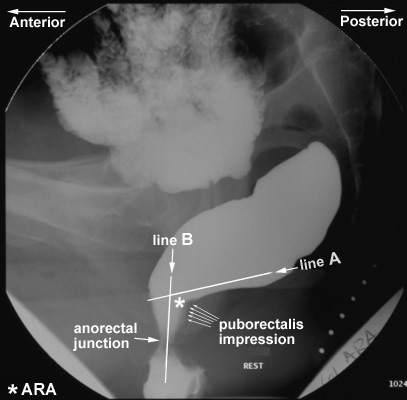

Anorectal angle (ARA)

- The puborectalis muscle, a component of the levator ani

muscle group, originates from one pubic bone, extends posteriorly around

the anorectal junction, and passes anteriorly again to attach to the other

side of the pubis. Thus, it forms a sling around the anorectal junction

and produces a posterior indentation on it.

- It is believed that fecal

continence depends not only on the intrinsic anal musculature but also on

a flap-valve effect produced by the puborectalis sling. This muscle is

tonic at rest and produces an angle of about 90° between the anal canal

and the lower rectum.

- The anorectal angle or

ARA (demonstrated by *

in the image below) is the angle

between a

line drawn parallel to the posterior wall of the rectal ampulla just above

the impression of the puborectalis sling (line A in the image below) and a line drawn in the axis of the anal canal (line

B in the image below).

- Changes in the ARA are representative of the activity of the

puborectalis muscle.

- Change in the ARA is measured during "squeeze" and

defecation with reference to the resting value.

- The ARA normally decreases

(becomes more acute) during squeezing, indicating contraction of the

pelvic floor musculature.

- The ARA normally increases (becomes more obtuse) when

the subject strains down to defecate, due to relaxation of the puborectalis muscle and loss of its posterior impression on the anorectal

junction. The range of normal ARA measurements is very wide (see

the table on the next page).